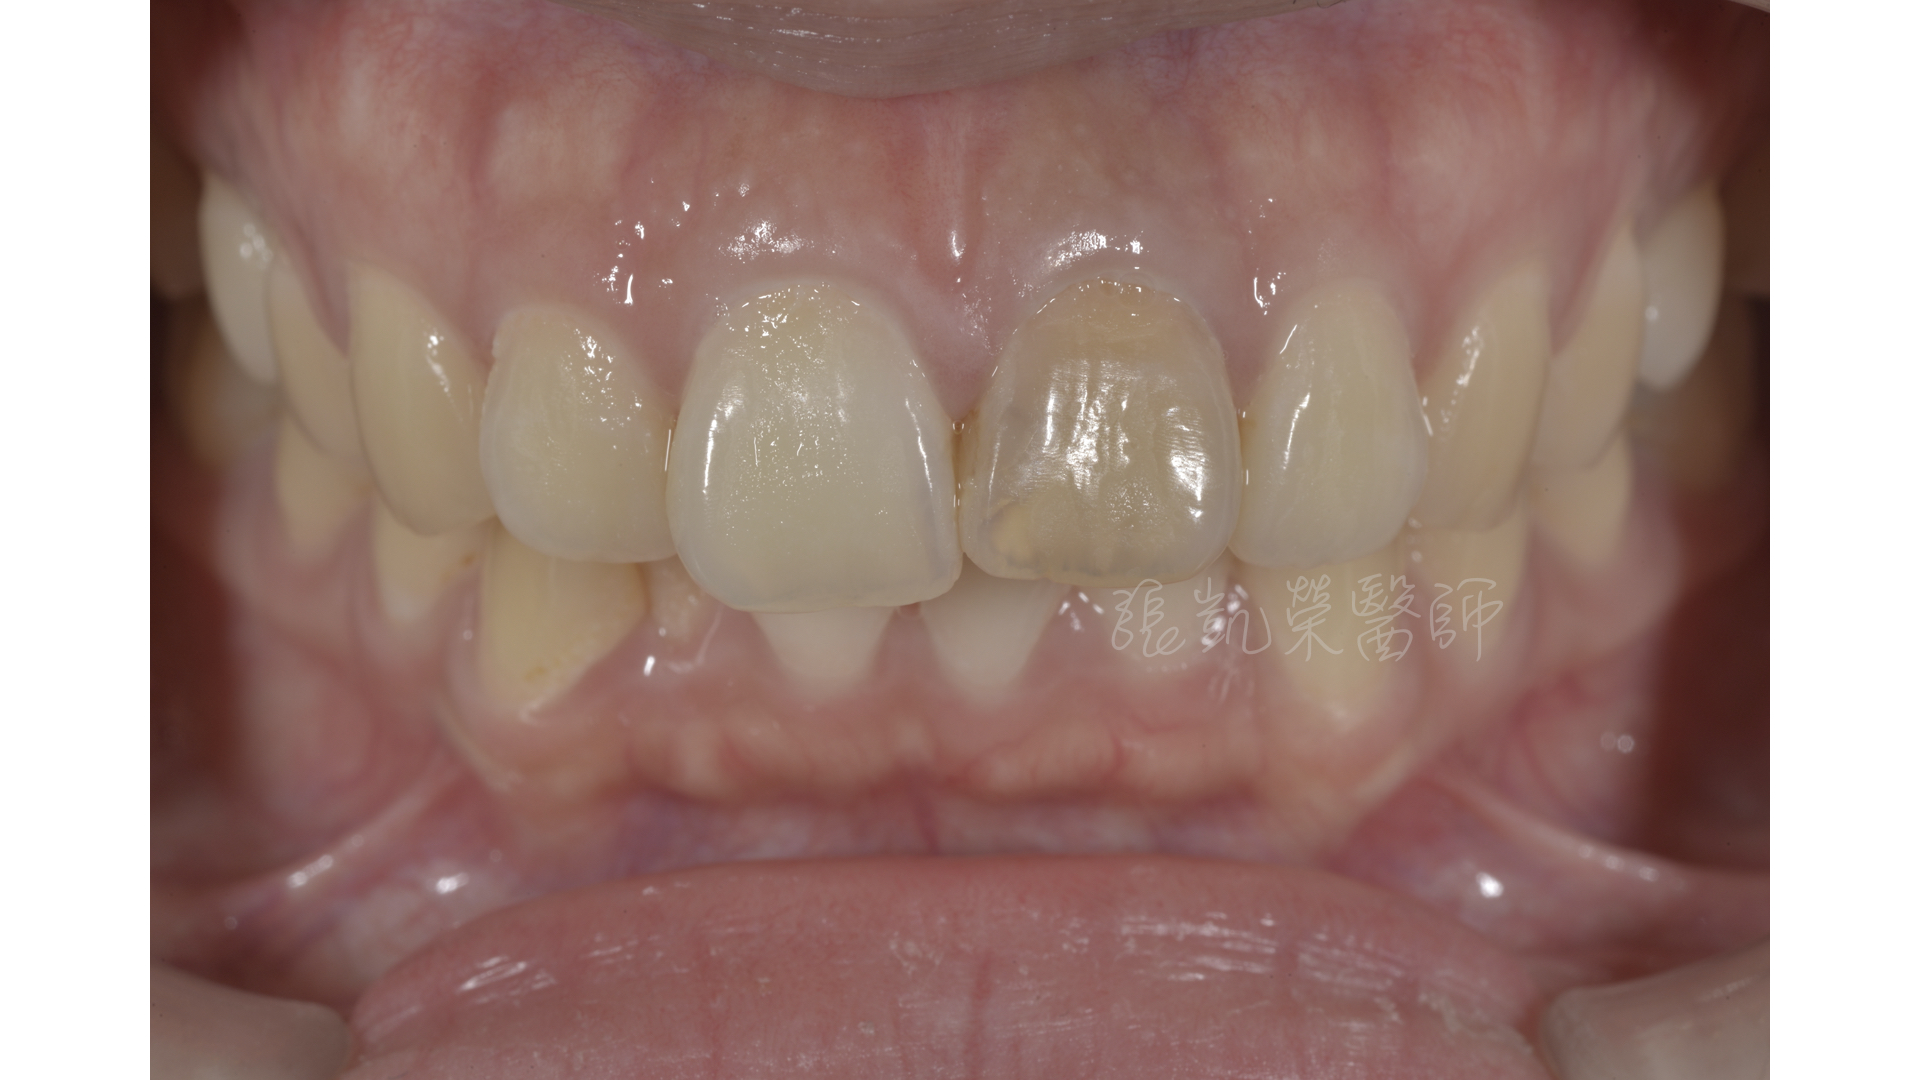

榮醫師,我左邊根管治療後的門牙,最近我覺得變黑了~~

檢查後,榮醫師發現,張小姐因為多年前牙齒撞到神經受傷,根管治療後持續到現在,除了牙冠牙色較暗之外,因為牙根也跟著變色,所以牙齦顏色也比較暗沈。